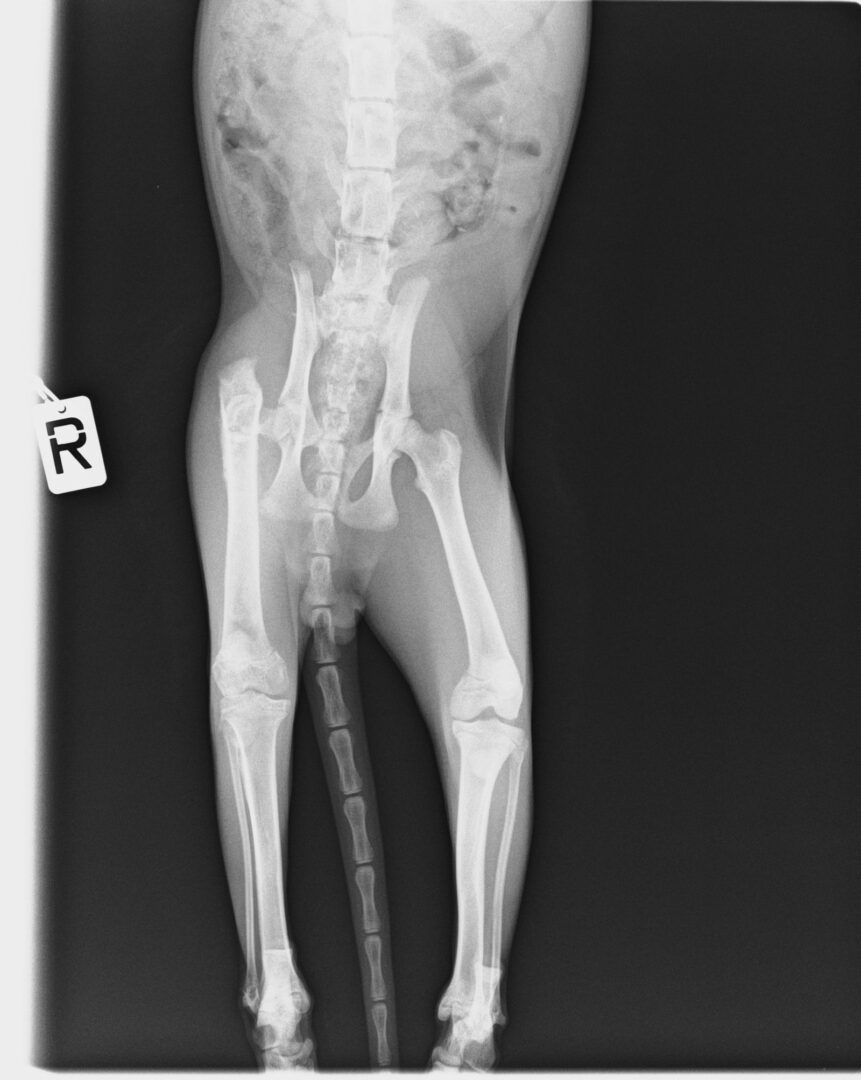

Der arme kleine, ca. 4 Monate alte Kater hat einen schlimmen Unfall überstanden.

Leider hat er einen schlimmen, schmerzhaften Bruch davon getragen, der morgen früh operiert werden muss.

Bitte drückt die Daumen, dass der kleine, 2kg leichte Kater die Operation morgen gut übersteht!